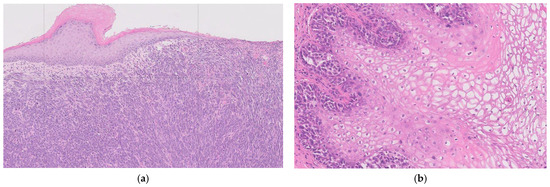

Figure 2. Histopathological Features for (a) Vulval Melanoma; Sections show a pigmented melanocytic lesion with evidence of junctional activity, marked cytological atypia, and invasion into the deep dermis. Growth is seen in both radial and vertical phases, with a brisk mitotic rate and perineural invasion. Melanin pigment is present within tumour cells. (b) Vaginal Melanoma; The tumour shows a polypoid architecture, often pigmented, with satellite nodules. Microscopy demonstrates solid, nested, and trabecular patterns, with a radial growth phase and brisk mitotic activity. Melanin is frequently present. Immunohistochemistry highlights S100 as the most sensitive marker.

Emerging evidence highlights the distinct molecular profile and tumour microenvironment seen in vulvovaginal melanoma, with variation evident even between vulval and vaginal sites. KITKIT mutations are more common in vulval melanomas (22–31% of cases) compared with vaginal melanomas (8%) [22,23]. Conversely, NRAS mutations are uncommon in vulval melanomas (10.2%) and appear to have a comparatively higher incidence in vaginal melanomas [22,23]. BRAF mutations are significantly less common in vulvovaginal melanomas, and TERT mutations may be entirely absent. Other frequently mutated genes include ATRX, SF3B1, B2M, NF1, and TP53 [23]. In terms of immunogenicity, vulvovaginal melanomas demonstrate lower rates of PD-L1 positivity (18%) compared with cutaneous melanomas (29.5%) and overall reduced expression of immune checkpoint genes. They also have a lower tumour mutational burden, in contrast to 46.9% of cutaneous melanomas, which display a high tumour mutational burden [23]. RNA deconvolution analysis of the tumour microenvironment further demonstrates reduced adaptive immune responses and decreased immunogenicity, with lower infiltration of immune-promoting macrophages, effector CD8+ T cells, and CD4+ T cells [23]. These distinct mutational and immune characteristics highlight vulvovaginal melanoma as a unique subclass of mucosal melanoma and may help explain its differential responses to systemic melanoma therapies (See Figure 2).